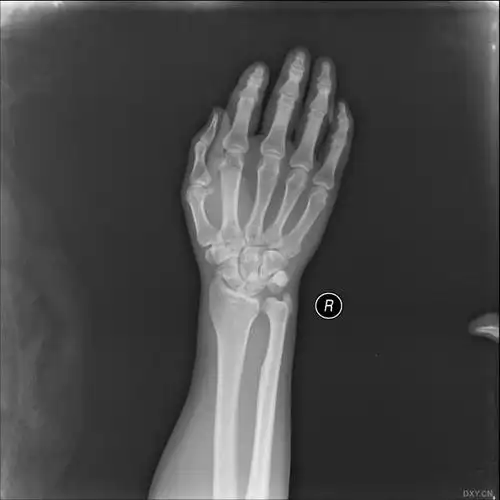

13岁女孩,不慎跌倒摔伤致右尺桡骨远端骨折,下尺桡关节脱位

下尺桡关节脱位一例

【读片】腕关节脱位 [病例帖]